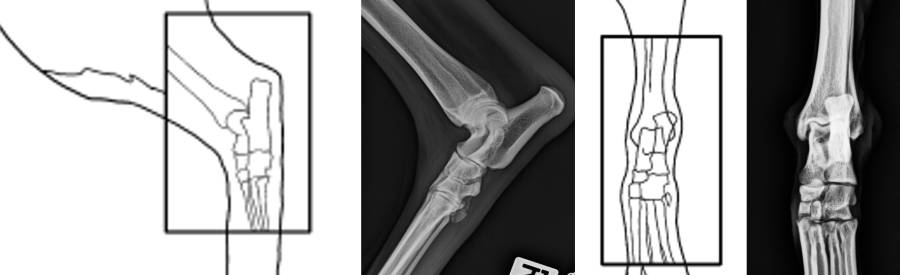

Röntgen Ellbogen

Röntgen Unterarm

Röntgen Karpus und Pfoten